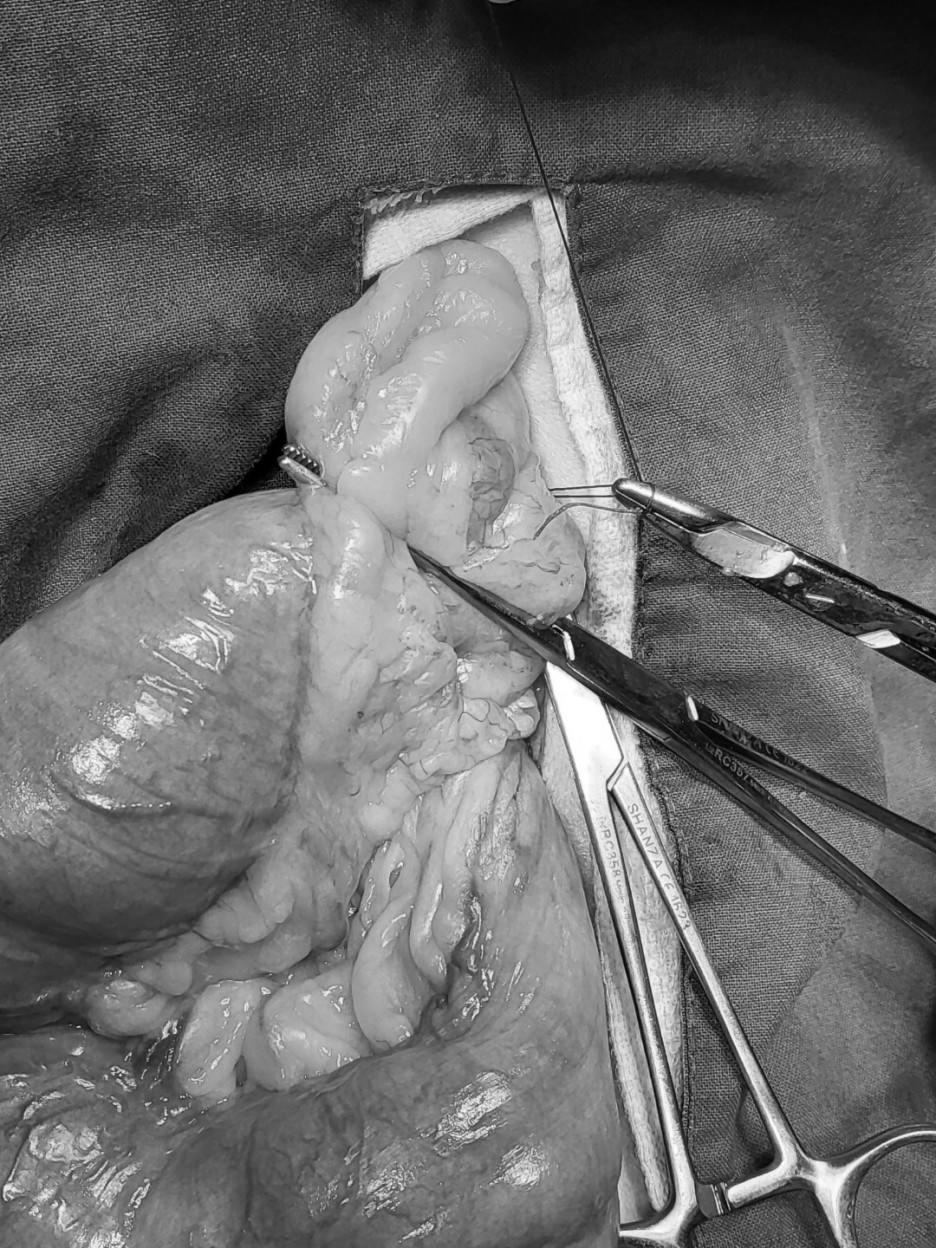

자궁노출 → 좌자궁각 및 난소절제 → 좌자궁각 혈관결찰

오른쪽 축 자궁각 혈관결 → 오른쪽 자궁각 및 난소절제 → 양쪽 자궁각 및 난소절제 후

호흡 마취 후 개복하여 양쪽 난소 및 자궁을 제거하였습니다.